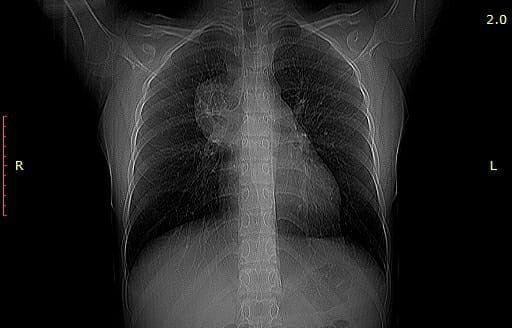

Опухоль в груди 15-летней девочки оказалась ее неразвившимся близнецом

Врачи ГБК им. Сперанского обнаружили у пациентки опухоль. Во время операции хирурги поняли, что новообразование содержит много разных видов тканей - жировую, хрящевую, волосы. Оказалось, что это неразвившийся плод близнеца пациентки.

Операция прошла успешно, жизни девочки ничего не угрожает.